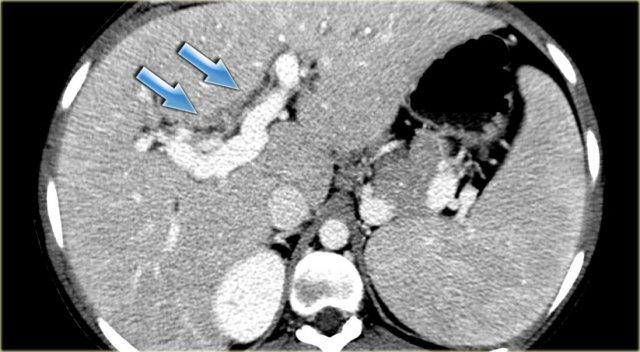

Bên trái là hình ảnh của một bệnh nhân có bệnh nặng hơn.

Chúng ta có thể thấy giãn đường mật nhẹ với hình ảnh gián đoạn.

Bên trái là hình ảnh của một bệnh nhân với các dấu hiệu CT rõ ràng hơn.

Hãy quan sát hình ảnh rồi tiếp tục đọc.

Các dấu hiệu bao gồm:

- Giãn không liên tục

- Thành ống mật dày tại vùng cuống gan

- Hạch bạch huyết to